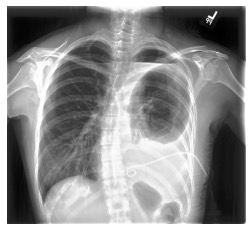

Automated diagnosis prediction from medical images is a valuable resource to support clinical decision-making. However, such systems usually need to be trained on large amounts of annotated data, which often is scarce in the medical domain. Zero-shot methods address this challenge by allowing a flexible adaption to new settings with different clinical findings without relying on labeled data. Further, to integrate automated diagnosis in the clinical workflow, methods should be transparent and explainable, increasing medical professionals' trust and facilitating correctness verification. In this work, we introduce Xplainer, a novel framework for explainable zero-shot diagnosis in the clinical setting. Xplainer adapts the classification-by-description approach of contrastive vision-language models to the multi-label medical diagnosis task. Specifically, instead of directly predicting a diagnosis, we prompt the model to classify the existence of descriptive observations, which a radiologist would look for on an X-Ray scan, and use the descriptor probabilities to estimate the likelihood of a diagnosis. Our model is explainable by design, as the final diagnosis prediction is directly based on the prediction of the underlying descriptors. We evaluate Xplainer on two chest X-ray datasets, CheXpert and ChestX-ray14, and demonstrate its effectiveness in improving the performance and explainability of zero-shot diagnosis. Our results suggest that Xplainer provides a more detailed understanding of the decision-making process and can be a valuable tool for clinical diagnosis.